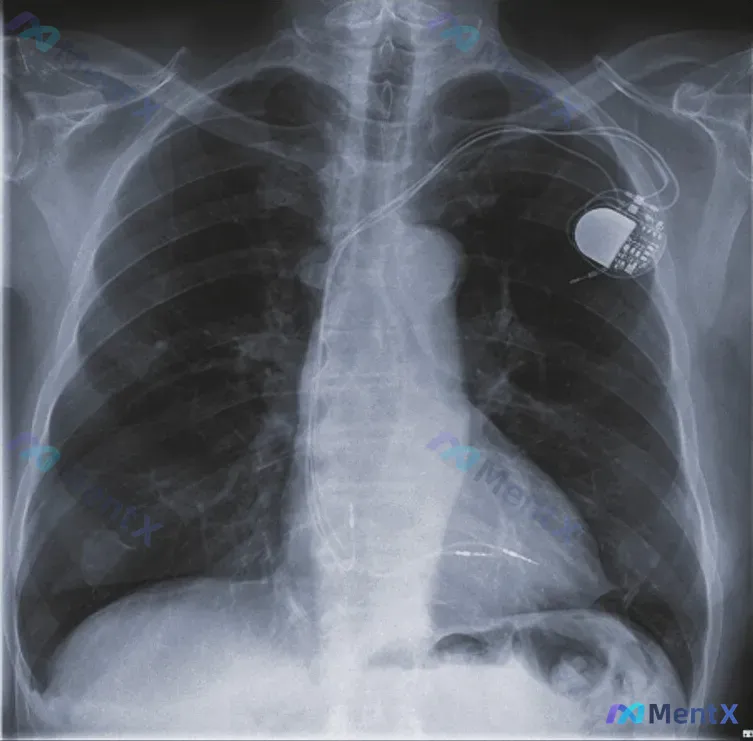

整理到一份术前胸部后前位X光片的病例资料,先看影像表现: - 左侧锁骨下区域可见起搏器(脉冲发生器)影; - 右心室内有两条心室起搏导线,其中一根处于未连接、被废弃的状态; - 其余:气管居中,纵隔无明显增宽,双肺野透亮度对称、肺纹理清晰走行自然,未见明显渗出/实变/肿块影;双侧肋膈角锐利,无胸腔积...